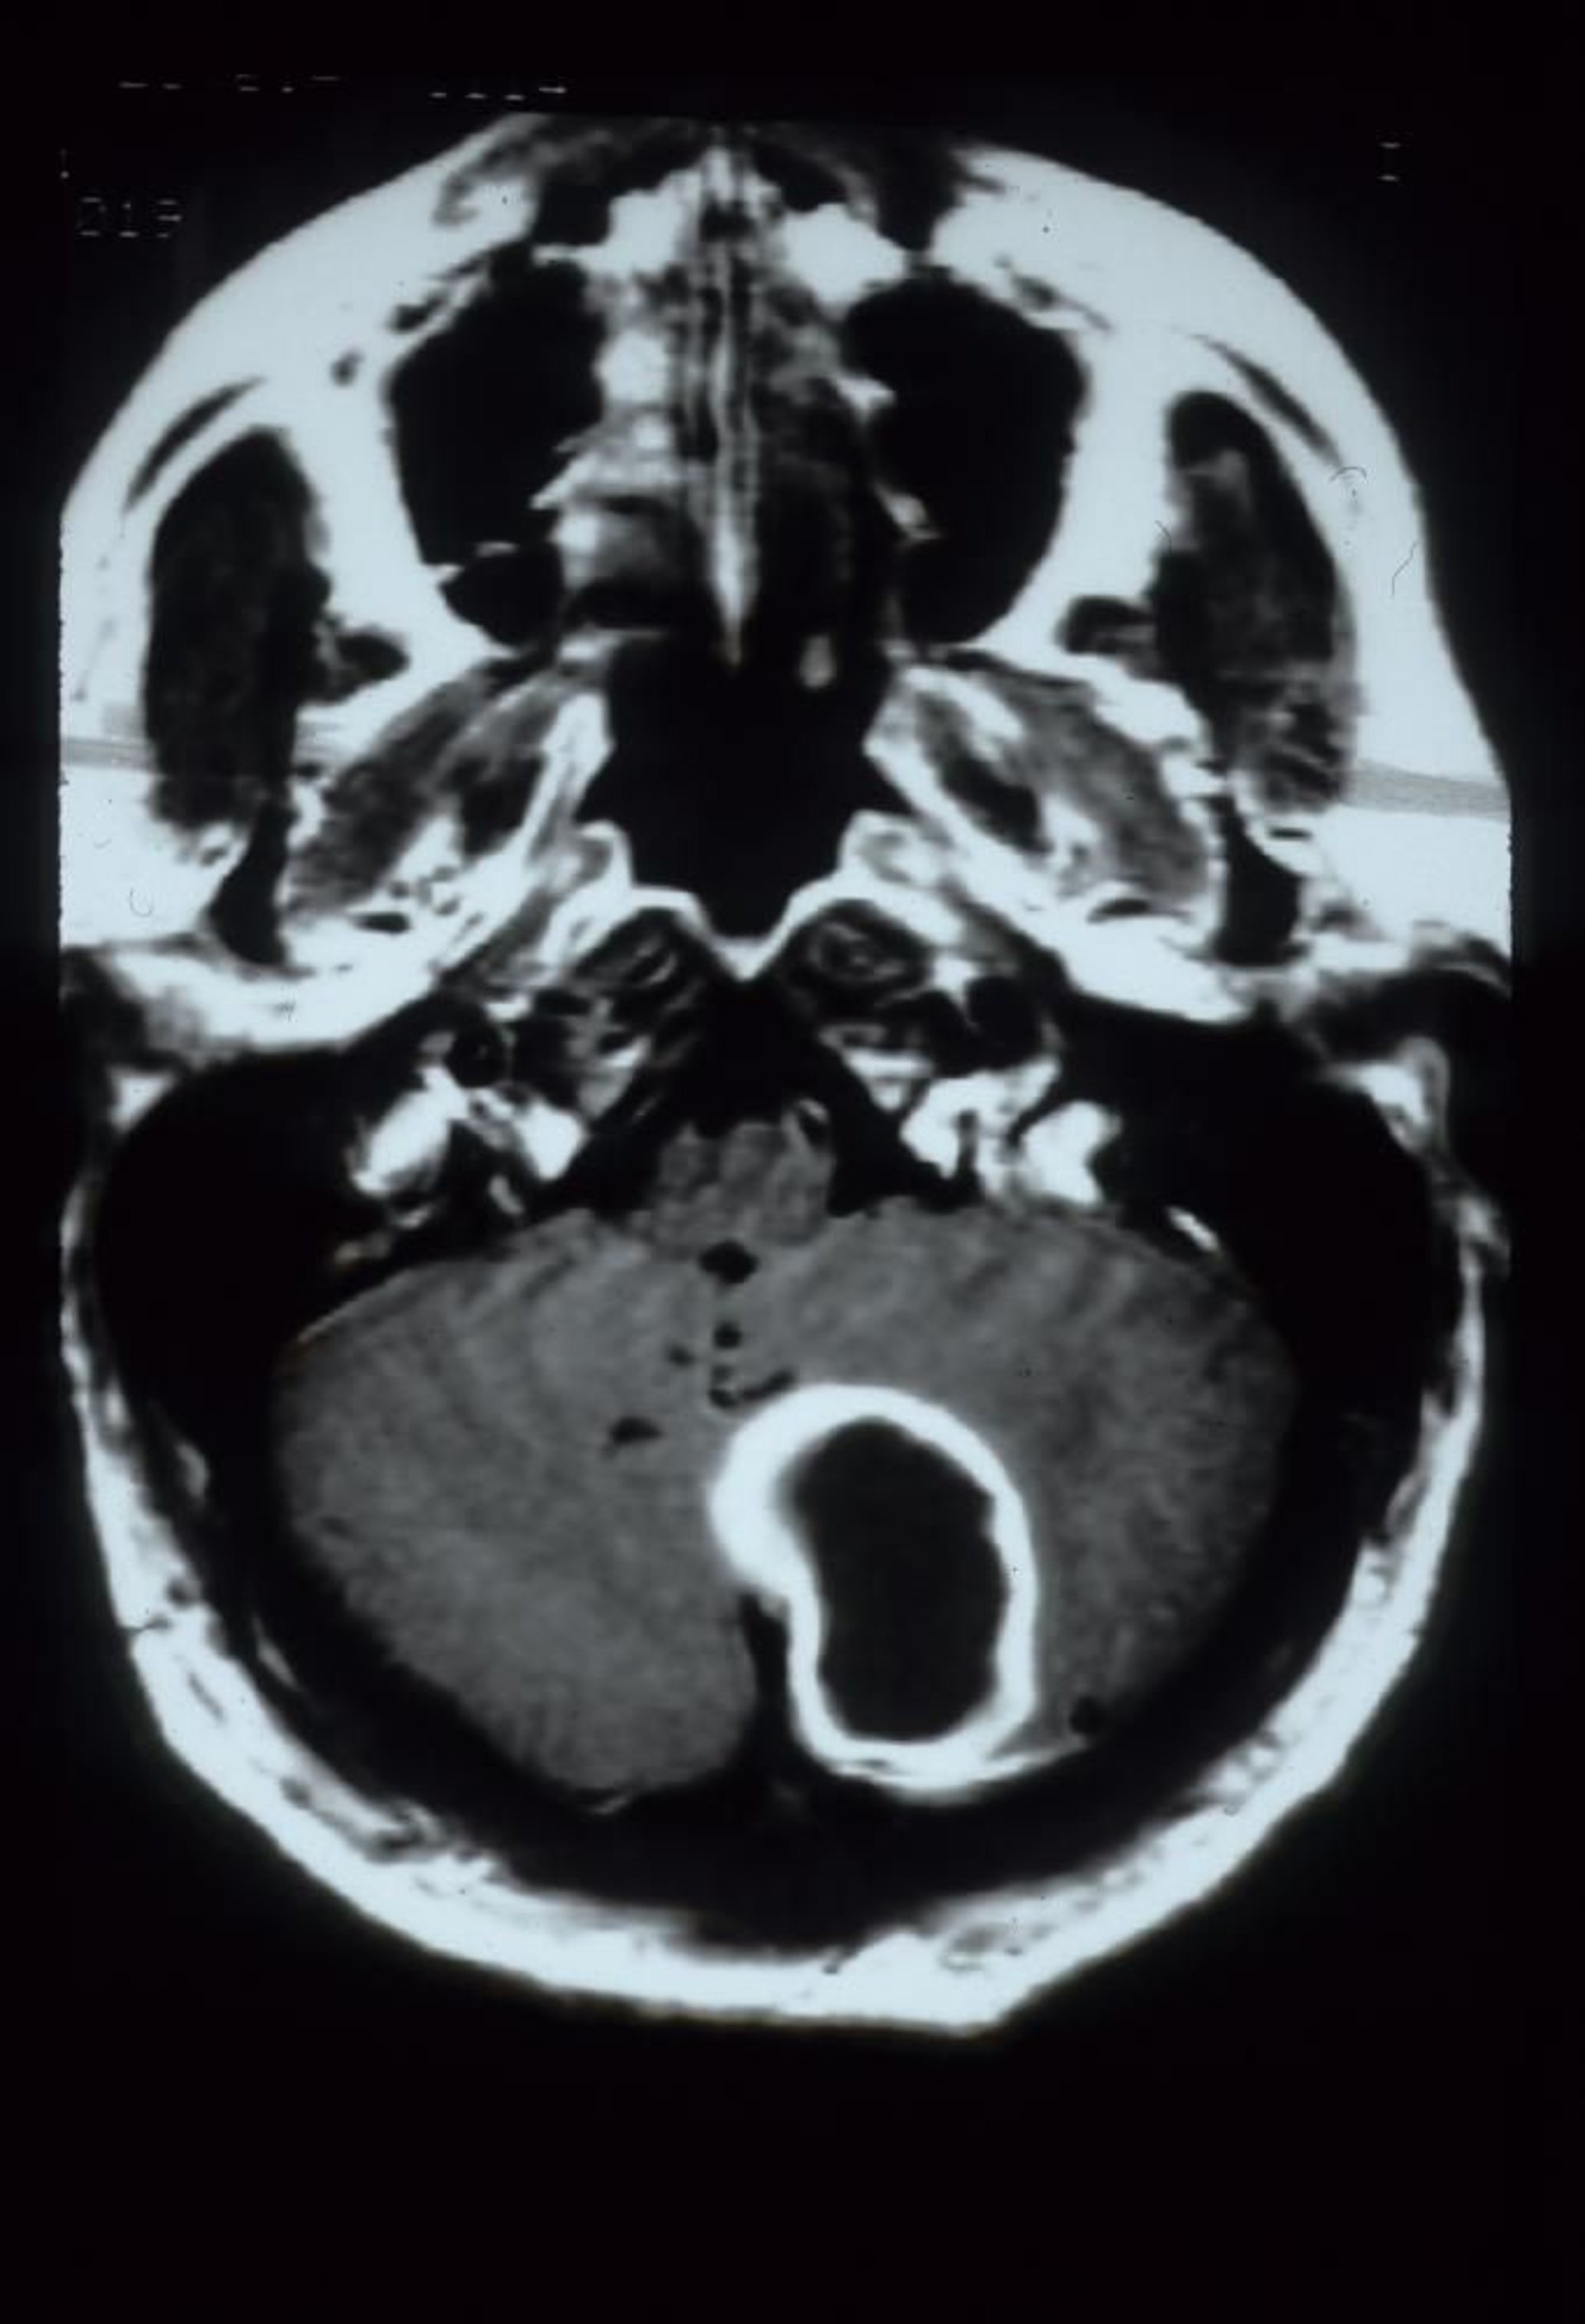

Абсцесс мозжечка

На этом МРТ-скане с контрастным усилением (гадолиний) показан абсцесс мозжечка, который проявляется в виде большого, увеличивающегося по краю полостного очага поражения в левом полушарии мозжечка.

Courtesy of John E. Greenlee, MD.